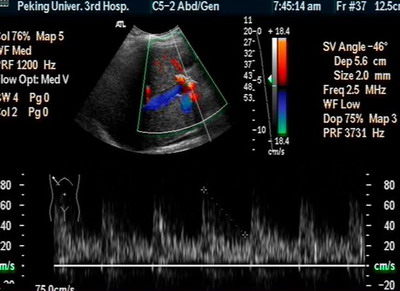

肝脏B超:右肝内及肝尾叶可见巨大强回声结节,9.3×8.8cm,边界欠清,后方回声增强。CDI:肿物周边可见肝动静脉绕行及肿物内门静脉穿行,无明显压迫现象。脾厚5.0cm肋下3.2cm脾门处脾静脉宽0.8cm

肝动脉、肠系膜上动脉、脾动脉造影见肝总动脉明显增粗,动脉期肝动脉及其分支显影良好,动脉早期可见门静脉显影,呈明显肝动脉—门静脉双轨征。肝实质期未见肿瘤染色。肠系膜上动脉间接门静脉显影,门静脉主干显影。门静脉血流方向为双向。可见胃底曲张血管逆行显影。